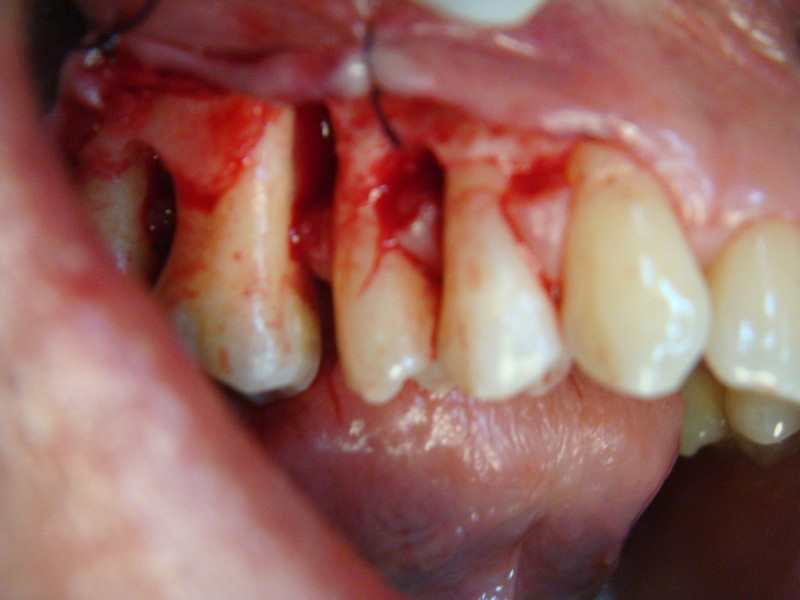

Chirurgia plastica Muco-Gengivale

Rigenerazione Gravi difetti parodontali

Rigenerazione difetto parodontale di un canino inferiore con materiale eterologo